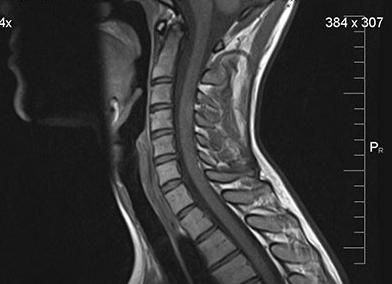

МРТ шейного отдела позвоночника

МРТ шеи помогает изучить структуру и строение позвонков, межпозвоночных дисков, спинного мозга и мягких тканей, выявить новообразования, нарушения кровообращения, патологии и аномалии развития, воспалительные процессы и заболевания в бессимптомной фазе.

В ходе диагностики врач получает серию срезов, на основании которой оценивает состояние тел позвонков, суставов, спинного мозга, межпозвоночных дисков, нервных корешков, которые выходят из спинномозгового канала, а также кровеносных сосудов.